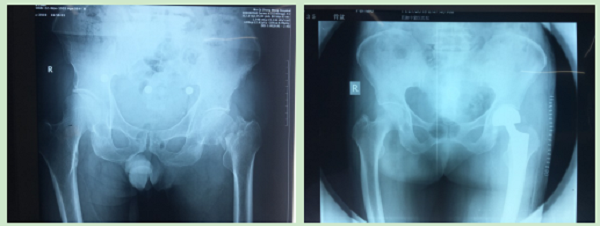

参与完成髋关节置换术、尺神经前置术、跟骨骨折钢板螺钉取出术、尺桡骨骨折钢板螺钉内固定取出术、掌骨骨折钢板螺钉取出术及清创缝合术等手术六例。